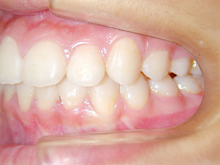

常滑市小林町在住 S.T様(15歳女性)

S.T様は下顎前歯の叢生が主訴でお母様と無料矯正相談で来院されました。

口を閉じる際に口元の緊張があり、横顔に突出感がありました。

以前に上顎前歯の部分矯正をされたご経験があるとお話しされておりました。

そのためか上顎犬歯の横幅(幅径)が通常より少なく思いました。

試料採取より診断の結果、上顎の前歯にも軽度の叢生があり、口元の緊張を改善し、

前歯の叢生の治療のために抜歯が必要であることを説明し、了承が得られたので本格矯正で治療をすすめることとなりました。

上顎前歯に軽度の叢生、下顎前歯に叢生がみられます前歯の上下の接触状態が緊密でなく軽度の舌癖の存在を疑います。

臼歯部は1歯 対 2歯で咬んでいます。